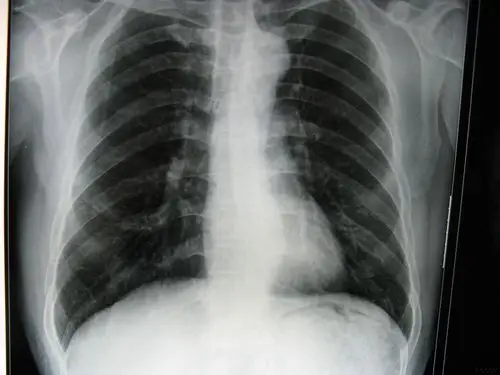

这张胸片肺部有问题吗?

疑难问题,看看这张胸片

求助:喘憋,无胸痛症状,胸片是立位

请高手观胸片

今天拍的胸片

胸片一张,可以帮我判断一下心影吗?